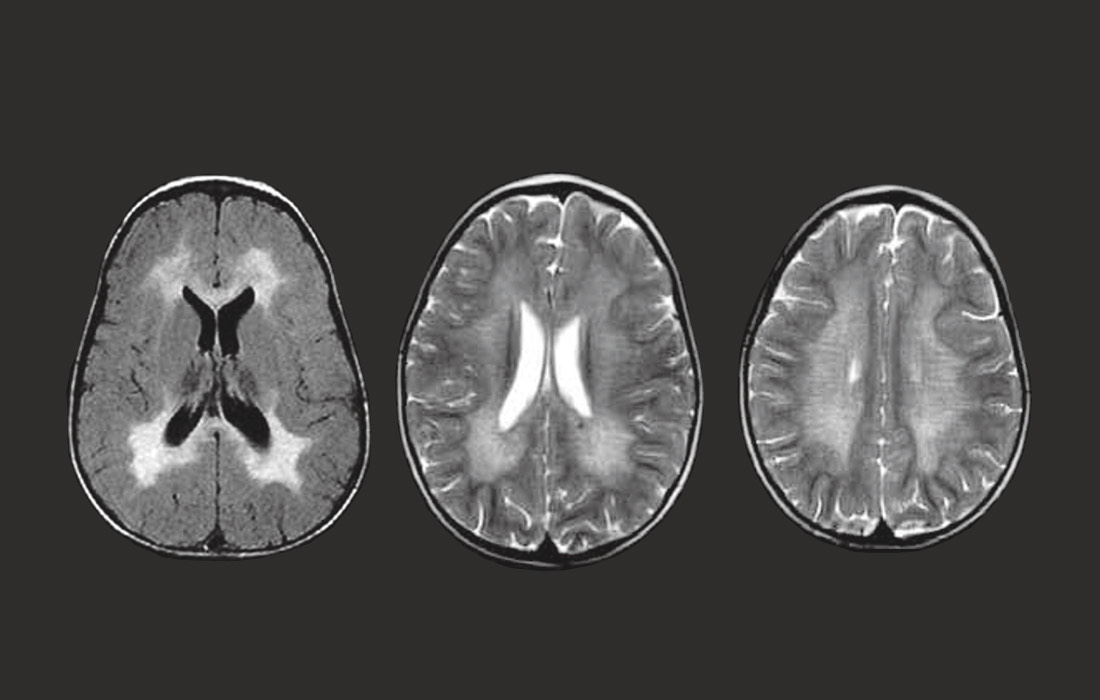

1784. Картина МРТ головного мозга, представленная на рисунке характерна для